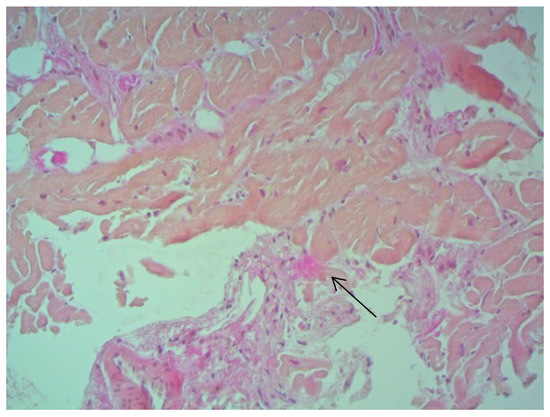

According to EMB results, no histological changes in the myocardium of the right ventricle (RV) were found in nine patients (13.4%). Fibrotic changes in the myocardium were detected in 26 cases (38.8%) including in predominantly perivascular fibrosis in 11 patients (42.3%), small focal fibrosis in eight patients (30.8%), and perimuscular fibrosis in seven patients (26.9%) (Figure 1, Figure 2 and Figure 3).

Figure 2. Small focal fibrosis in IVS ×200, staining according to Van Gieson. The arrow indicates the focus of connective tissue proliferation.